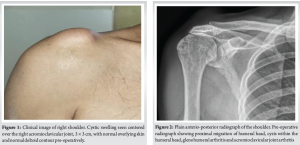

A 77-year-old male patient with right hand dominance, a known case of hypertension and diabetes, came to the outpatient department with a gradually increasing swelling over his right shoulder (Fig. 1) for the past 6 months. He was diagnosed with a frozen shoulder, having no history of trauma, 5 years ago, and recovered with a complete range of motion within a year. He gave a history of redeveloping shoulder pain 2 years ago, which disappeared within 6 months of onset. He had no limitations in his daily activities and continued to use his right hand with dominance. Sleeping on the right side was occasionally painful.

On examination, the shoulder swelling was globular, soft, cystic, fluctuant measuring 3 × 3 cm centered over the AC joint with the overlying skin stretched. There was no anterior joint tenderness or subacromial tenderness. The range of motion was comparable to the opposite side – forward flexion of 160°, abduction of 110° and near-normal internal and external rotations. The movements were associated with crepitus over the AC joint but no pain. Special tests revealed intact, but weak cuff muscles. Plain radiographs revealed superior migration of the humeral head, a sourcil sign of the greater tuberosity, glenohumeral and AC joint arthritis (Fig. 2). The MRI showed synovial thickening, degenerative changes in the AC joint and glenohumeral joint with a hyper-intense homogeneous cystic swelling above the AC joint on T2-weighted imaging (Fig. 3). There was a cut-off geyser sign with no communication to the AC joint or glenohumeral joint (Fig. 4). The supraspinatus was partially intact but atrophied. Considering the patients asymptomatic shoulder, wait and watch approach was considered for a period of 2 months for spontaneous regression. There was no subsidence in the size of the swelling and hence, the patient returned for removal of the lesion.